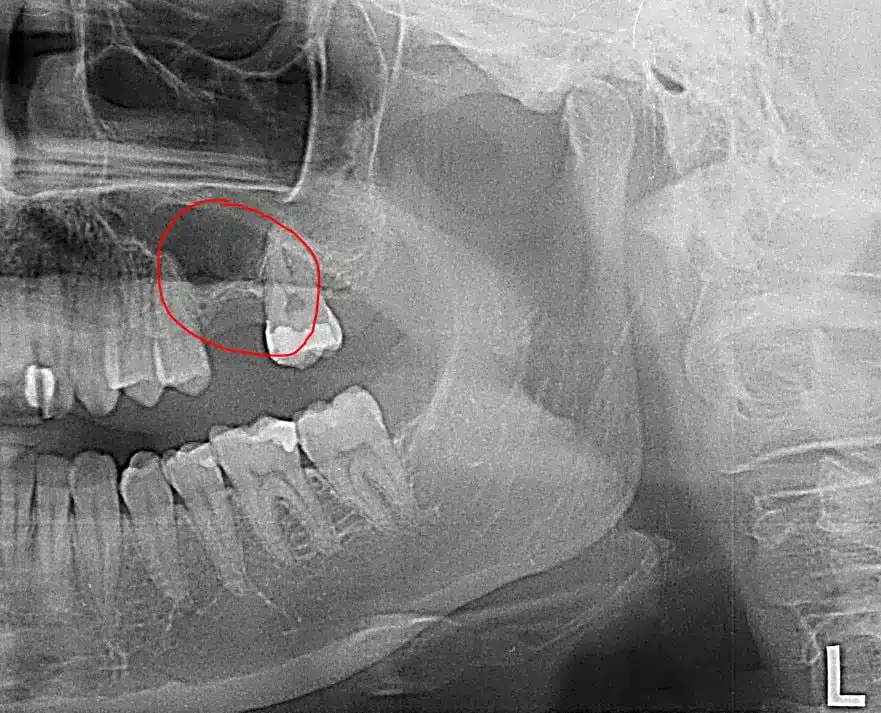

Cuando nos extraen una muela y no optamos por reponerla, es normal preguntarse qué consecuencias puede tener. La pérdida de una pieza puede afectar a la estética, a la mordida y a la salud bucal con el tiempo. Aquí te lo explicamos sin humo.

Tras una extracción, el cuerpo “interpreta” que esa zona ya no se usa y puede empezar la reabsorción ósea. Reponer la pieza ayuda a mantener función, estabilidad y una mordida más equilibrada.

- Desplazamiento dental: los dientes vecinos pueden moverse hacia el hueco.

- Pérdida ósea: con el tiempo puede dificultar tratamientos futuros.